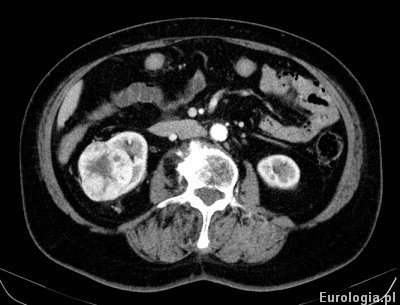

Fot. Guz prawej nerki - obraz w tomografii komputerowej.